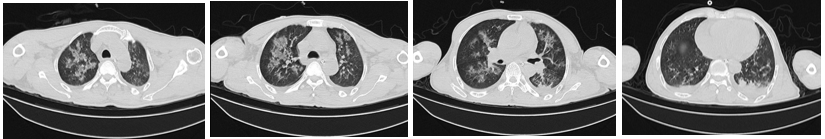

50岁出头的奉师傅(化名)在一家工厂上班,最近在上班后突然出现了咳嗽、发热的症状。在当地诊所用药以后,咳嗽症状并没有缓解,反而很快出现了呼吸困难,随后前往当地医院就诊。根据医院胸部CT结果显示,奉师傅“双肺见弥漫性斑片状、片状密度增高影及磨玻璃密度影(呈双侧“大白肺”改变)”。医院初步拟“重症肺炎”行抗感染治疗。然而,患者病情进展很快,并伴有呼吸衰竭的症状,血氧饱和度下降至85%。由于当地医院抢救治疗效果不佳,奉师傅被紧急转移至广州市第一人民医院呼吸与危重医学科监护室进行抢救。

文章配图

当地医院胸部CT: 双肺见弥漫性斑片状、片状密度增高影及磨玻璃密度影